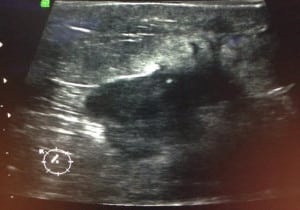

Caso 1.

((Imagen del mismo Nódulo por ultrasonido: se ve un nódulo sólido de márgenes angulados, altera el tejido que esta adyacente))